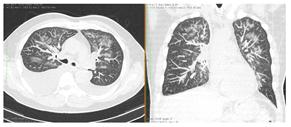

2. Наличие клинических проявлений, указанных в п. 1, в сочетании с характерными изменениями в легких по данным компьютерной томографии (КТ) (см. Приложение 1 настоящих рекомендаций) вне зависимости от результатов однократного лабораторного исследования на наличие РНК SARS-CoV-2 и эпидемиологического анамнеза.

- Изменения при КТ (рентгенографии), типичные для вирусного поражения (объем поражения минимальный или средний; КТ 1-2)

- Изменения в легких при КТ (рентгенографии), типичные для вирусного поражения (объем поражения значительный или субтотальный; КТ 3-4)

- Изменения в легких при КТ (рентгенографии), типичные для вирусного поражения критической степени (объем поражения значительный или субтотальный; КТ 4) или картина ОРДС.

КТ имеет высокую чувствительность в выявлении изменений в легких, характерных для COVID-19. Применение КТ целесообразно для первичной оценки состояния ОГК у пациентов с тяжелыми прогрессирующими формами заболевания, а также для дифференциальной диагностики выявленных изменений и оценки динамики процесса. КТ позволяет выявить характерные изменения в легких у пациентов с COVID-19 еще до появления положительных лабораторных тестов на инфекцию с помощью МАНК. В то же время, КТ выявляет изменения легких у значительного числа пациентов с бессимптомной и легкой формами заболевания, которым не требуется госпитализация. Результаты КТ в этих случаях не влияют на тактику лечения и прогноз заболевания при наличии лабораторного подтверждения COVID-19. Поэтому массовое применение КТ для скрининга асимптомных и легких форм болезни не рекомендуется.